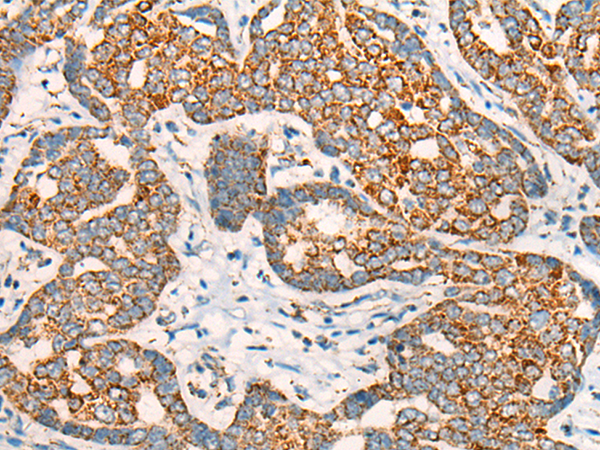

分类: 科研抗体货号: P09471别名:应用: IHC反应种属: Human, Mouse